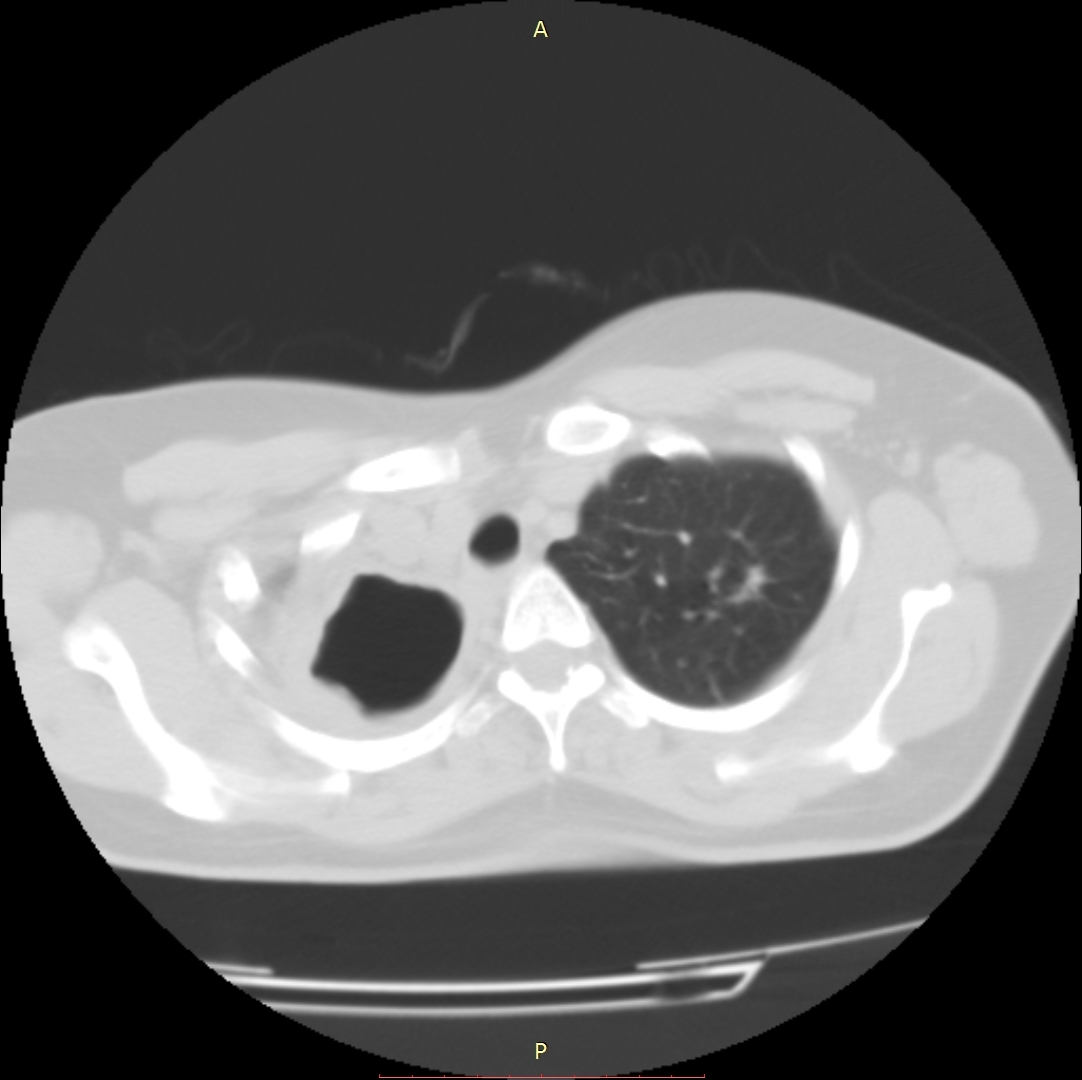

პაციენტი 37 წლის ქალი. 1997 წ-ს გაკეთებული აქვს მარჯვენა ზედა წილის რეზექცია ფილტვის ტუბერკულოზის გამო. წლების განმავლობაში აქვს გამწვავებები, რაც გამოიხატება მაღალი ცხელებით, ხველით, დიდი რაოდენობით სისხლნარევი, მძაფრი სუნის მქონე ნახველის გამოყოფით. რენტგენოლოგიურად ინახა დიდი ზომის ღრუ მარჯვენა ფილტვის ზედა ველში. ბრონქოსკოპიით ინახა დიდი ზომის მარჯვენა ზ/წილოვანი ბრონქის ტაკვის ფისტულა. ტაკვის სიგრძე იძლეოდა ბლოკატორის ჩადგმის შესაძლებლობას. რიგიდული ბრონქოსკოპით მარჯვენა ზ/წილოვან ბრონქში ჩაიდგა MEDLUNG-ის ბლოკატორი N13. რამოდენიმე საათში საჭირო გახდა ბლოკატორის გამოცვლა ნაკლებ (N12) ზომაზე განვითარებული მარჯვენა ქვედა წილის ატელექტაზის გამო. მანიპულაციის შემდეგ პაციენტს შეუწყდა სისხლნარევი და ჩირქოვანი სეკრეტი. 10 თვის შემდეგ საკონტროლო გამოკვლევით ღრუს ადგილას დაფიქსირდა ფიბროთორაქსი. უახლოეს მომავალში, გულმკერდის კტ კვლევის შემდეგ, იგეგმება ბლოკატორის ამოღება.